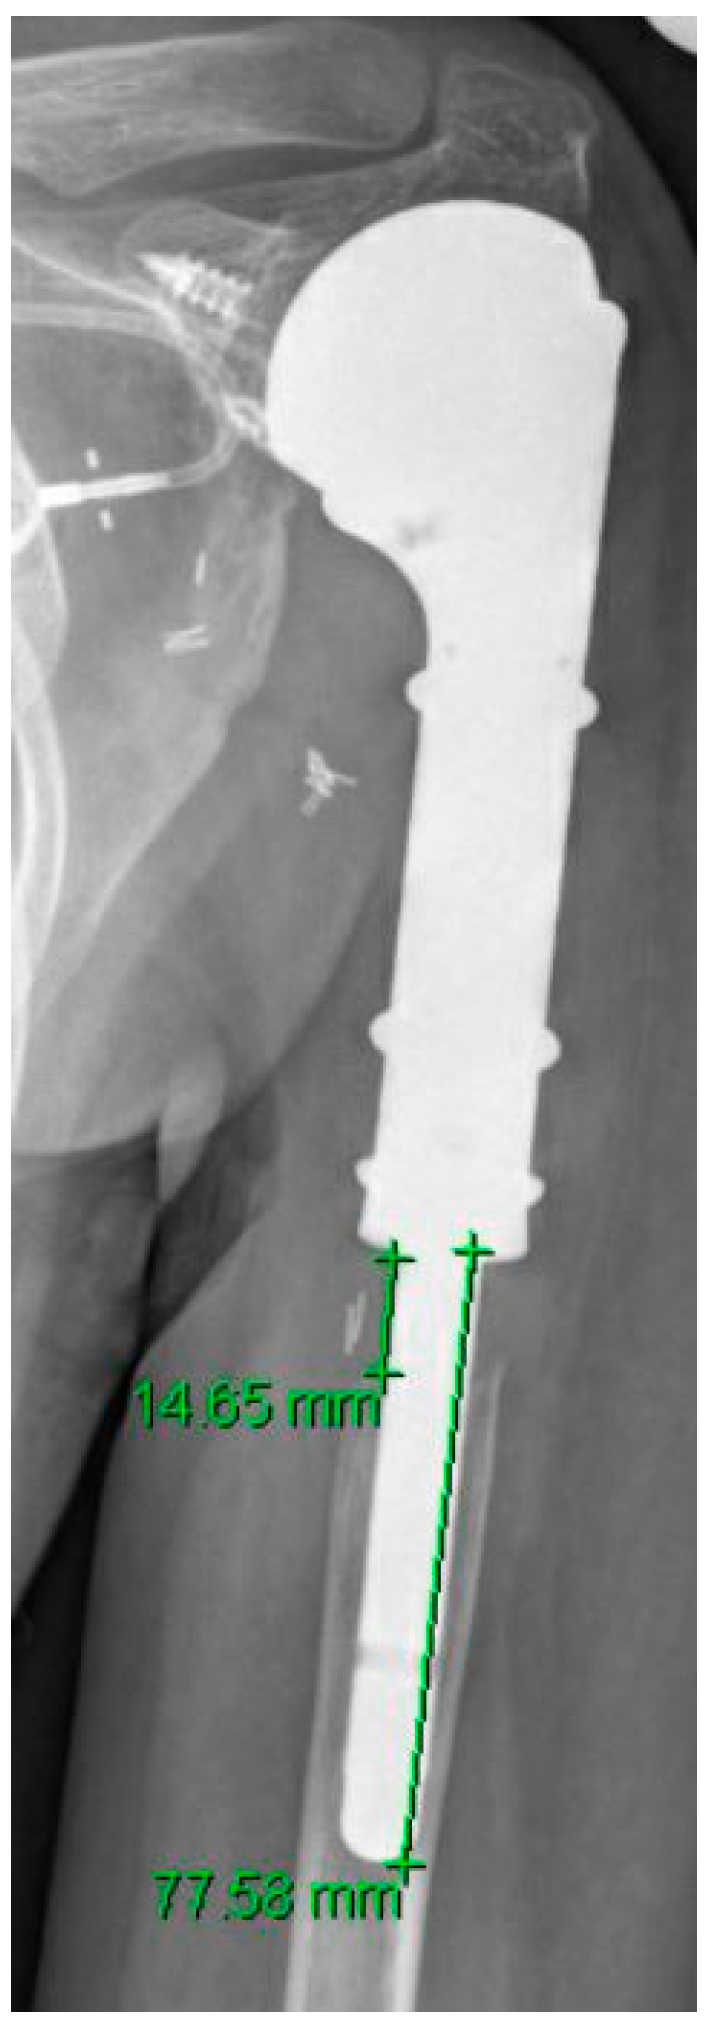

| Size of humeral stem | 75mm |

| Extent Stress Shielding Median (IQR) | p Value | |

|---|---|---|

| All patients | 14% (8–25) | |

| Male | 14% (10–45) | 0.06 |

| Female | 11% (5–21) | 0.06 |

| History of chemotherapy | 16% (10–40) | 0.012 |

| No history of chemotherapy | 10% (6–14) | 0.012 |

| History of radiotherapy | 7% (5–21) | 0.08 |

| No history of radiotherapy | 14% (9–28) | 0.08 |

| Intraarticular resection | 12% (7–26) | 0.43 |

| Extraarticular resection | 17% (8–24) | 0.43 |

| Reverse endoprosthesis | 14% (10–29) | 0.47 |

| Anatomical hemiarthroplasty | 17% (8–24) | 0.47 |